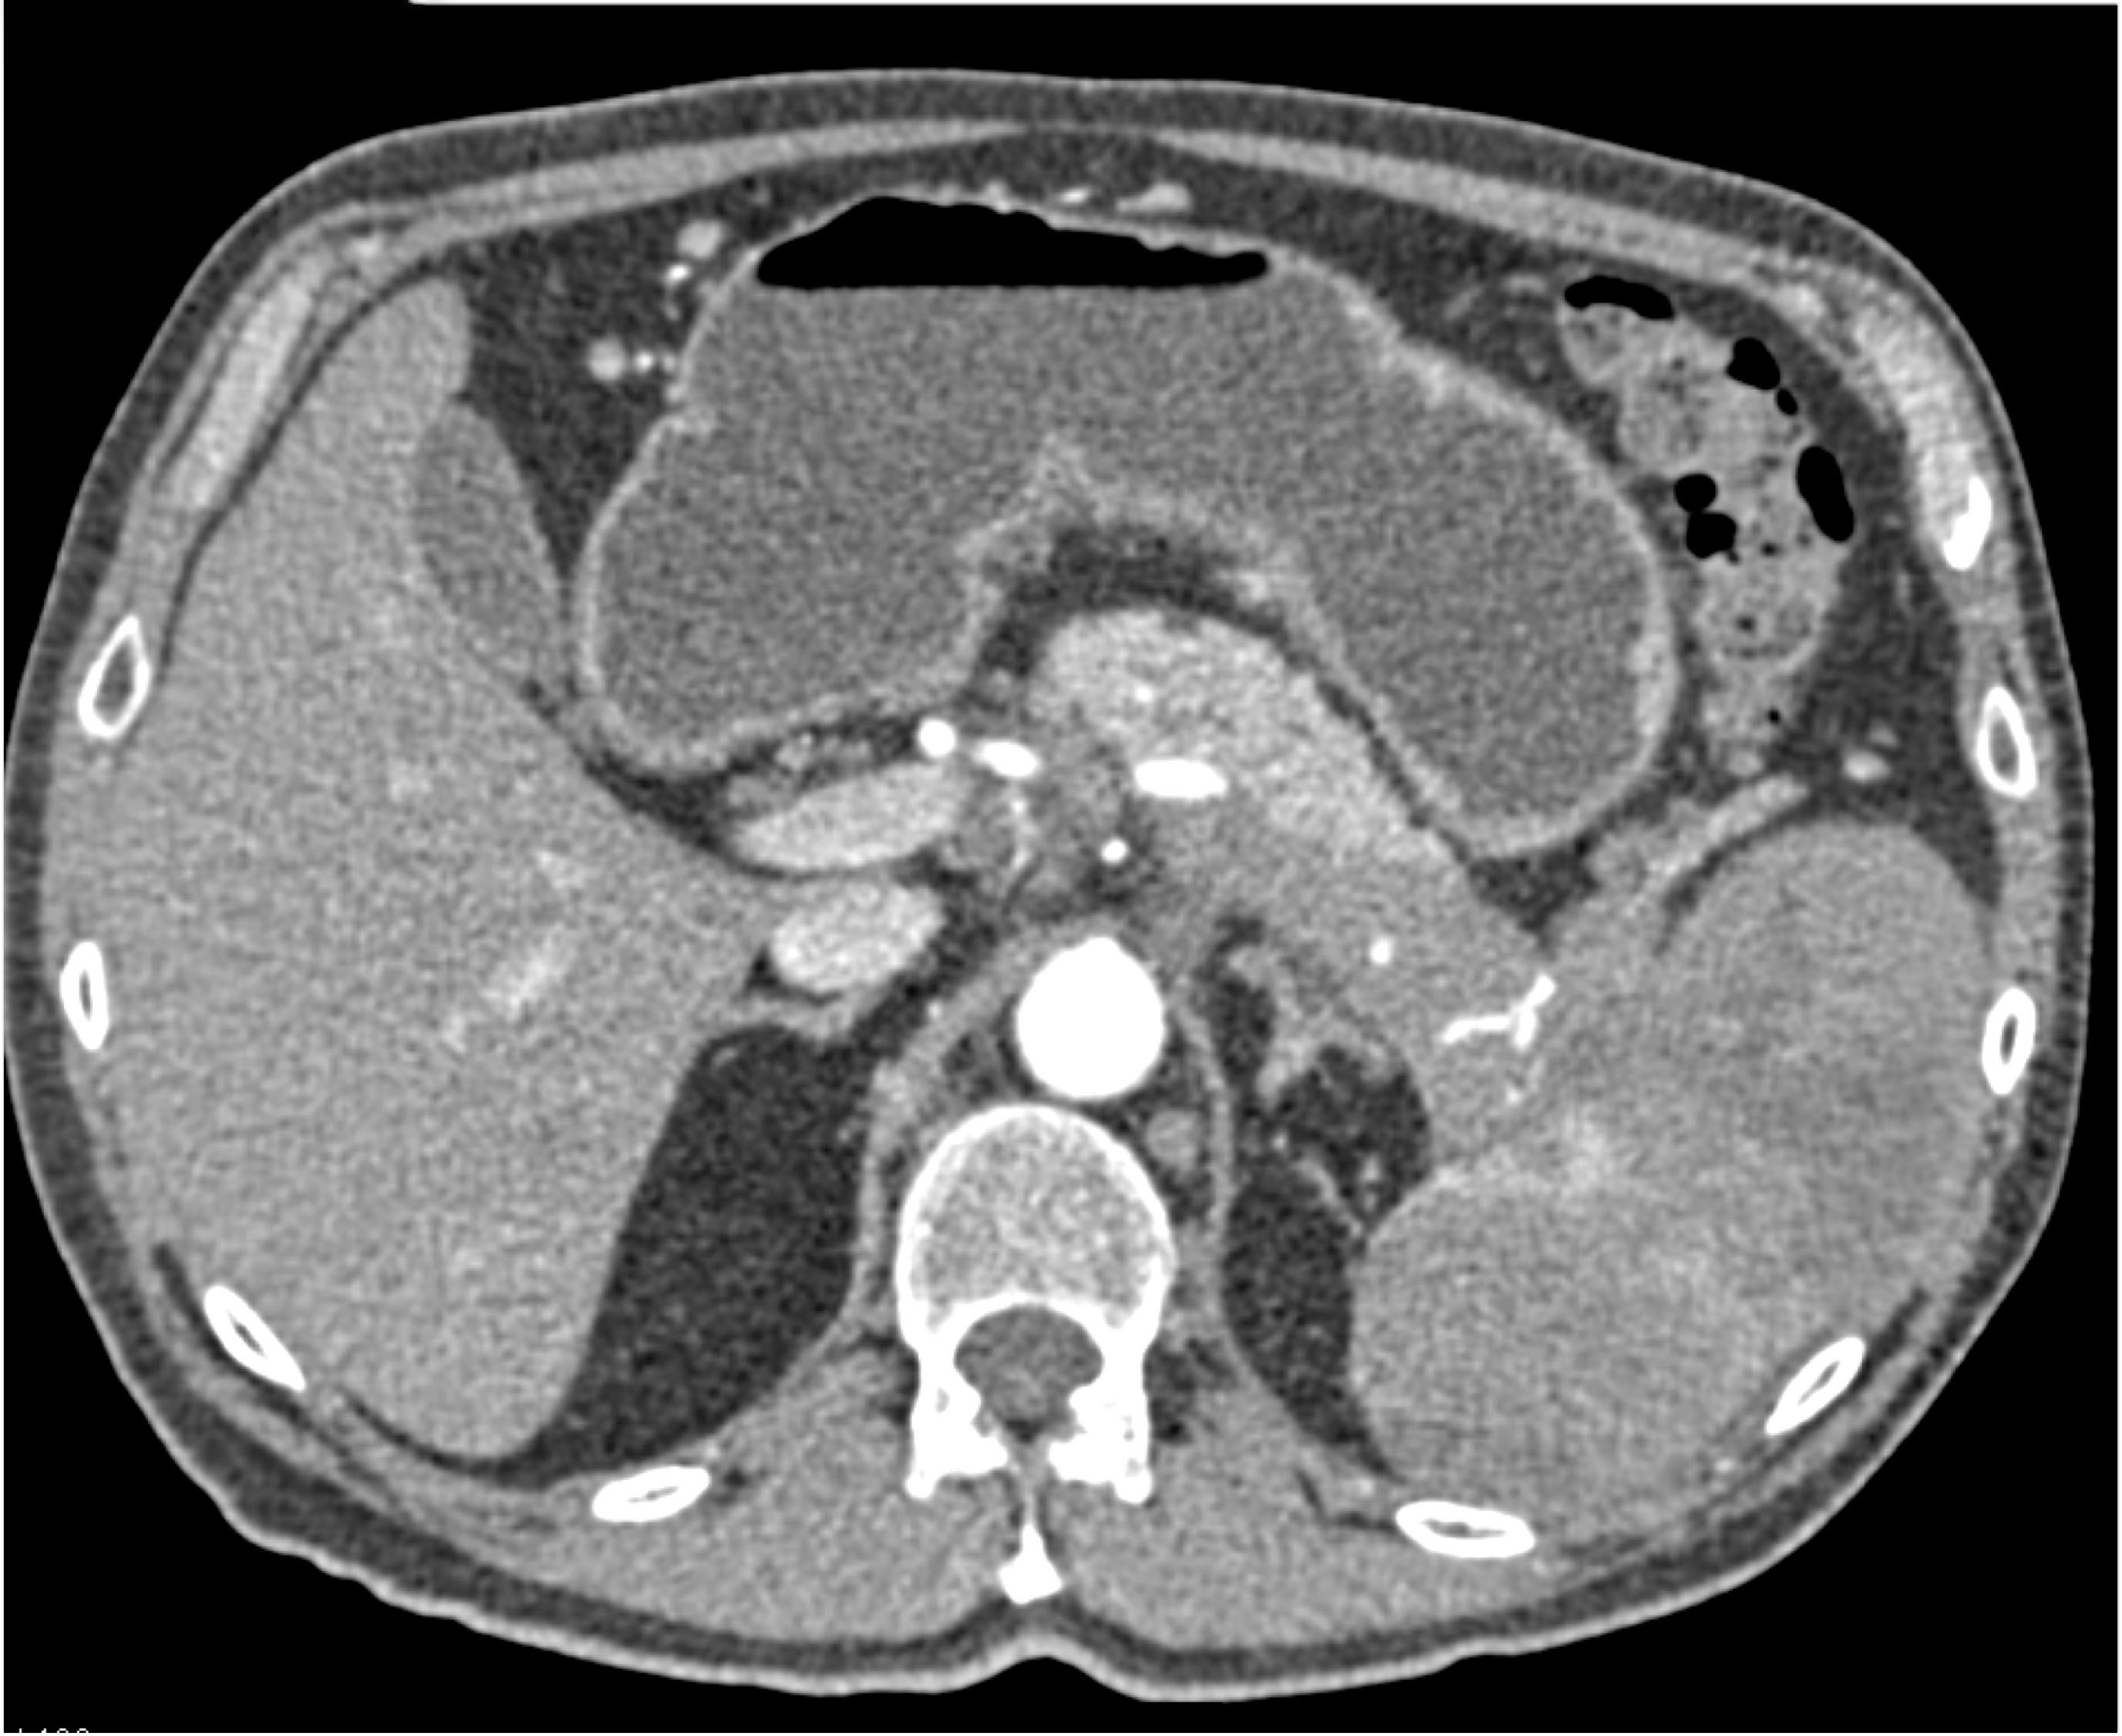

- Evaluate the CT images of each question carefully.

- Click on thumbnail images to view a larger version of the images.

- Take time to make the call on the diagnosis for each individual question.